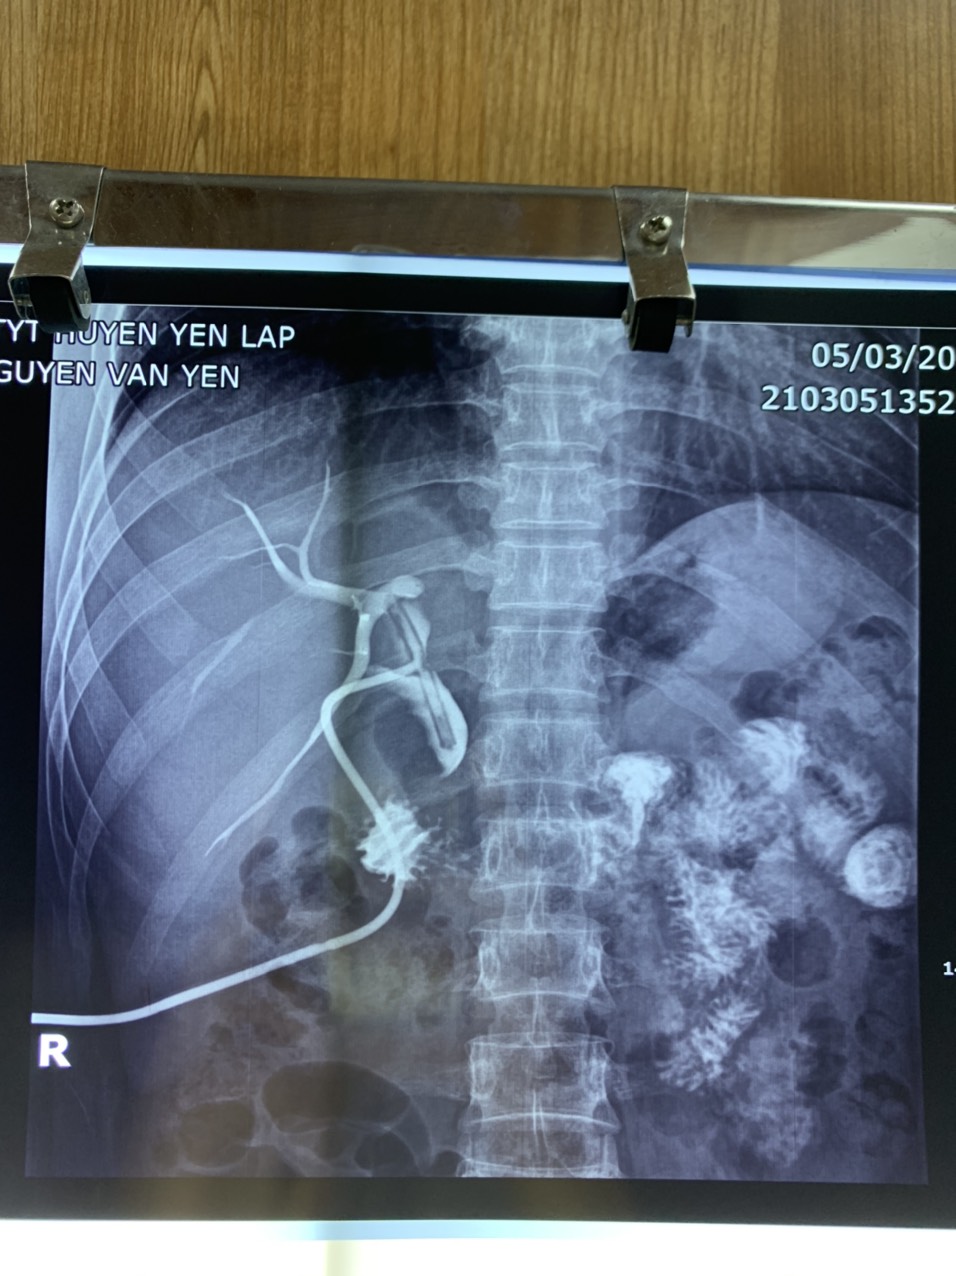

Người bệnh N.V.Y, 30 tuổi ở Tâm Bưởi, xã Đồng Thịnh có tiền sử sỏi ống mật chủ, sỏi túi mật đã điều trị nội khoa tuy nhiên bệnh vẫn tái phát nhiều lần. Ngày 23/02/2021, người bệnh đến khám tại Trung tâm Y tế huyện Yên Lập với triệu chứng đau tức nhiều vùng hạ sườn phải nhiều ngày, vàng da, củng mạc mắt vàng nhẹ. Kết quả xét nghiệm các chỉ số đường mật tăng, men gan tăng. Phim chụp CT Scaner cho thấy ống mật chủ giãn, có nhiều sỏi, sỏi lớn nhất KT 20x24mm.

Sau ca phẫu thuật, hiện tại sức khỏe người bệnh đã ổn định, da hết vàng. Người bệnh được làm các cận lâm sàng sau phẫu thuật, có kết quả các chỉ số xét nghiệm bình thường, men gan giảm về giới hạn bình thường, men tụy bình thường, hình ảnh chụp CT Scaner tiêm thuốc cản quang cho thấy sỏi đã được lấy ra hoàn toàn, đường mật thông. Người bệnh được ra viện sau 2 tuần điều trị và dự kiến sẽ rút Kerh sau 1 tháng.